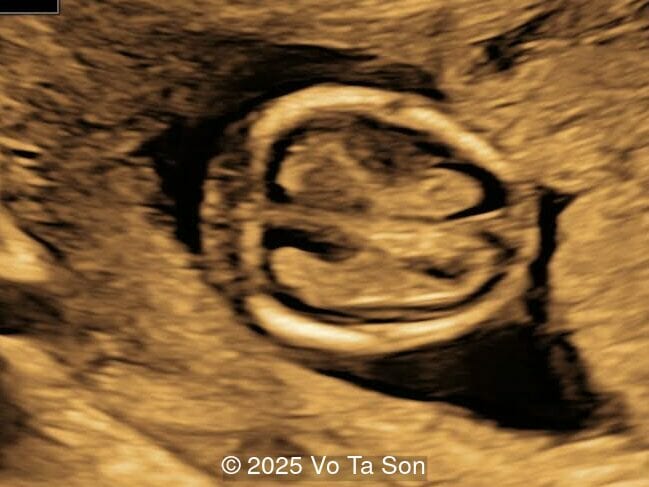

A woman underwent routine prenatal screening at 13 weeks. The non-invasive prenatal test (NIPT) showed low risk for common aneuploidies including trisomy 21, 18, and 13. However, first-trimester anomaly scan revealed multiple fetal anomalies.

Please describe the abnormalities and provide a syndromic diagnosis that best fits the presentation.